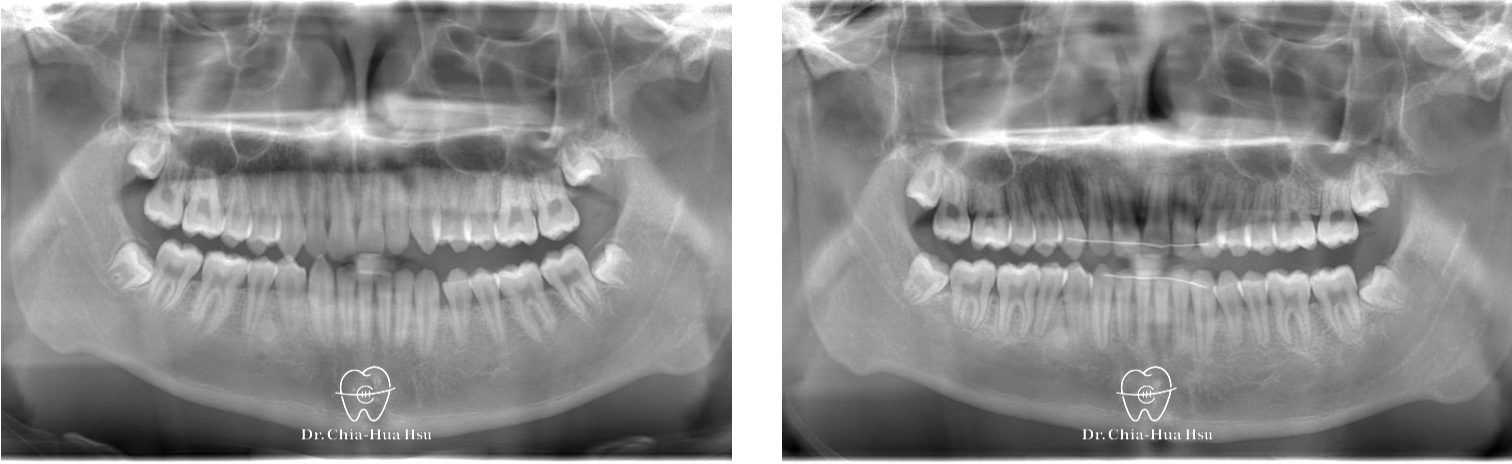

治療前

治療後